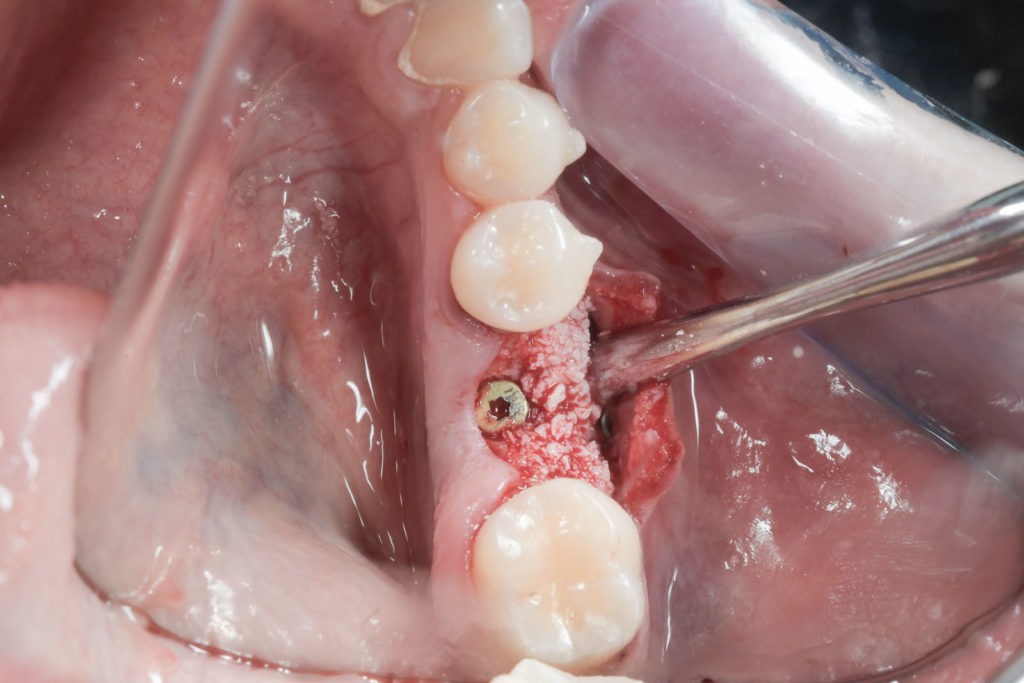

Zabieg odbudowy zębodołu powinno się wykonać możliwe jak najszybciej po usunięciu zęba. Jego celem jest odbudowa naturalnej objętości kości w miejscu utraconego zęba, a następnie szybkie wprowadzenie implantu. Najlepsze rezultaty uzyskuje się przy zastosowaniu biomateriału w formie bloczków kolagenowych lub granulatu, które dają trwałe efekty odbudowy oraz optymalną funkcję i estetykę odtworzonych koron zębów na wszczepionym implancie.

Bloki kolagenowe używane są najczęściej do odbudowy geometrycznych, trójwymiarowych ubytków kostnych, których doskonałym przykładem jest zębodół po ekstrakcji zęba. Jest to jeden ze sposobów na procedurę „socket preservation”, czyli natychmiastową lub wczesną odbudowę zębodołów poekstrakcyjnych dla osiągnięcia optymalnych efektów estetycznej odbudowy protetycznej koron zębów na implantach.